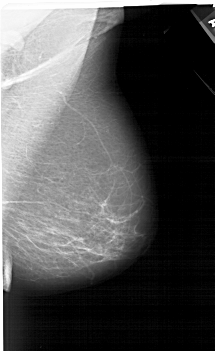

A_1207_1.RIGHT_MLO

LEFT_MLO LINES 6496 PIXELS_PER_LINE 3451 BITS_PER_PIXEL 12 RESOLUTION 43.5 OVERLAY